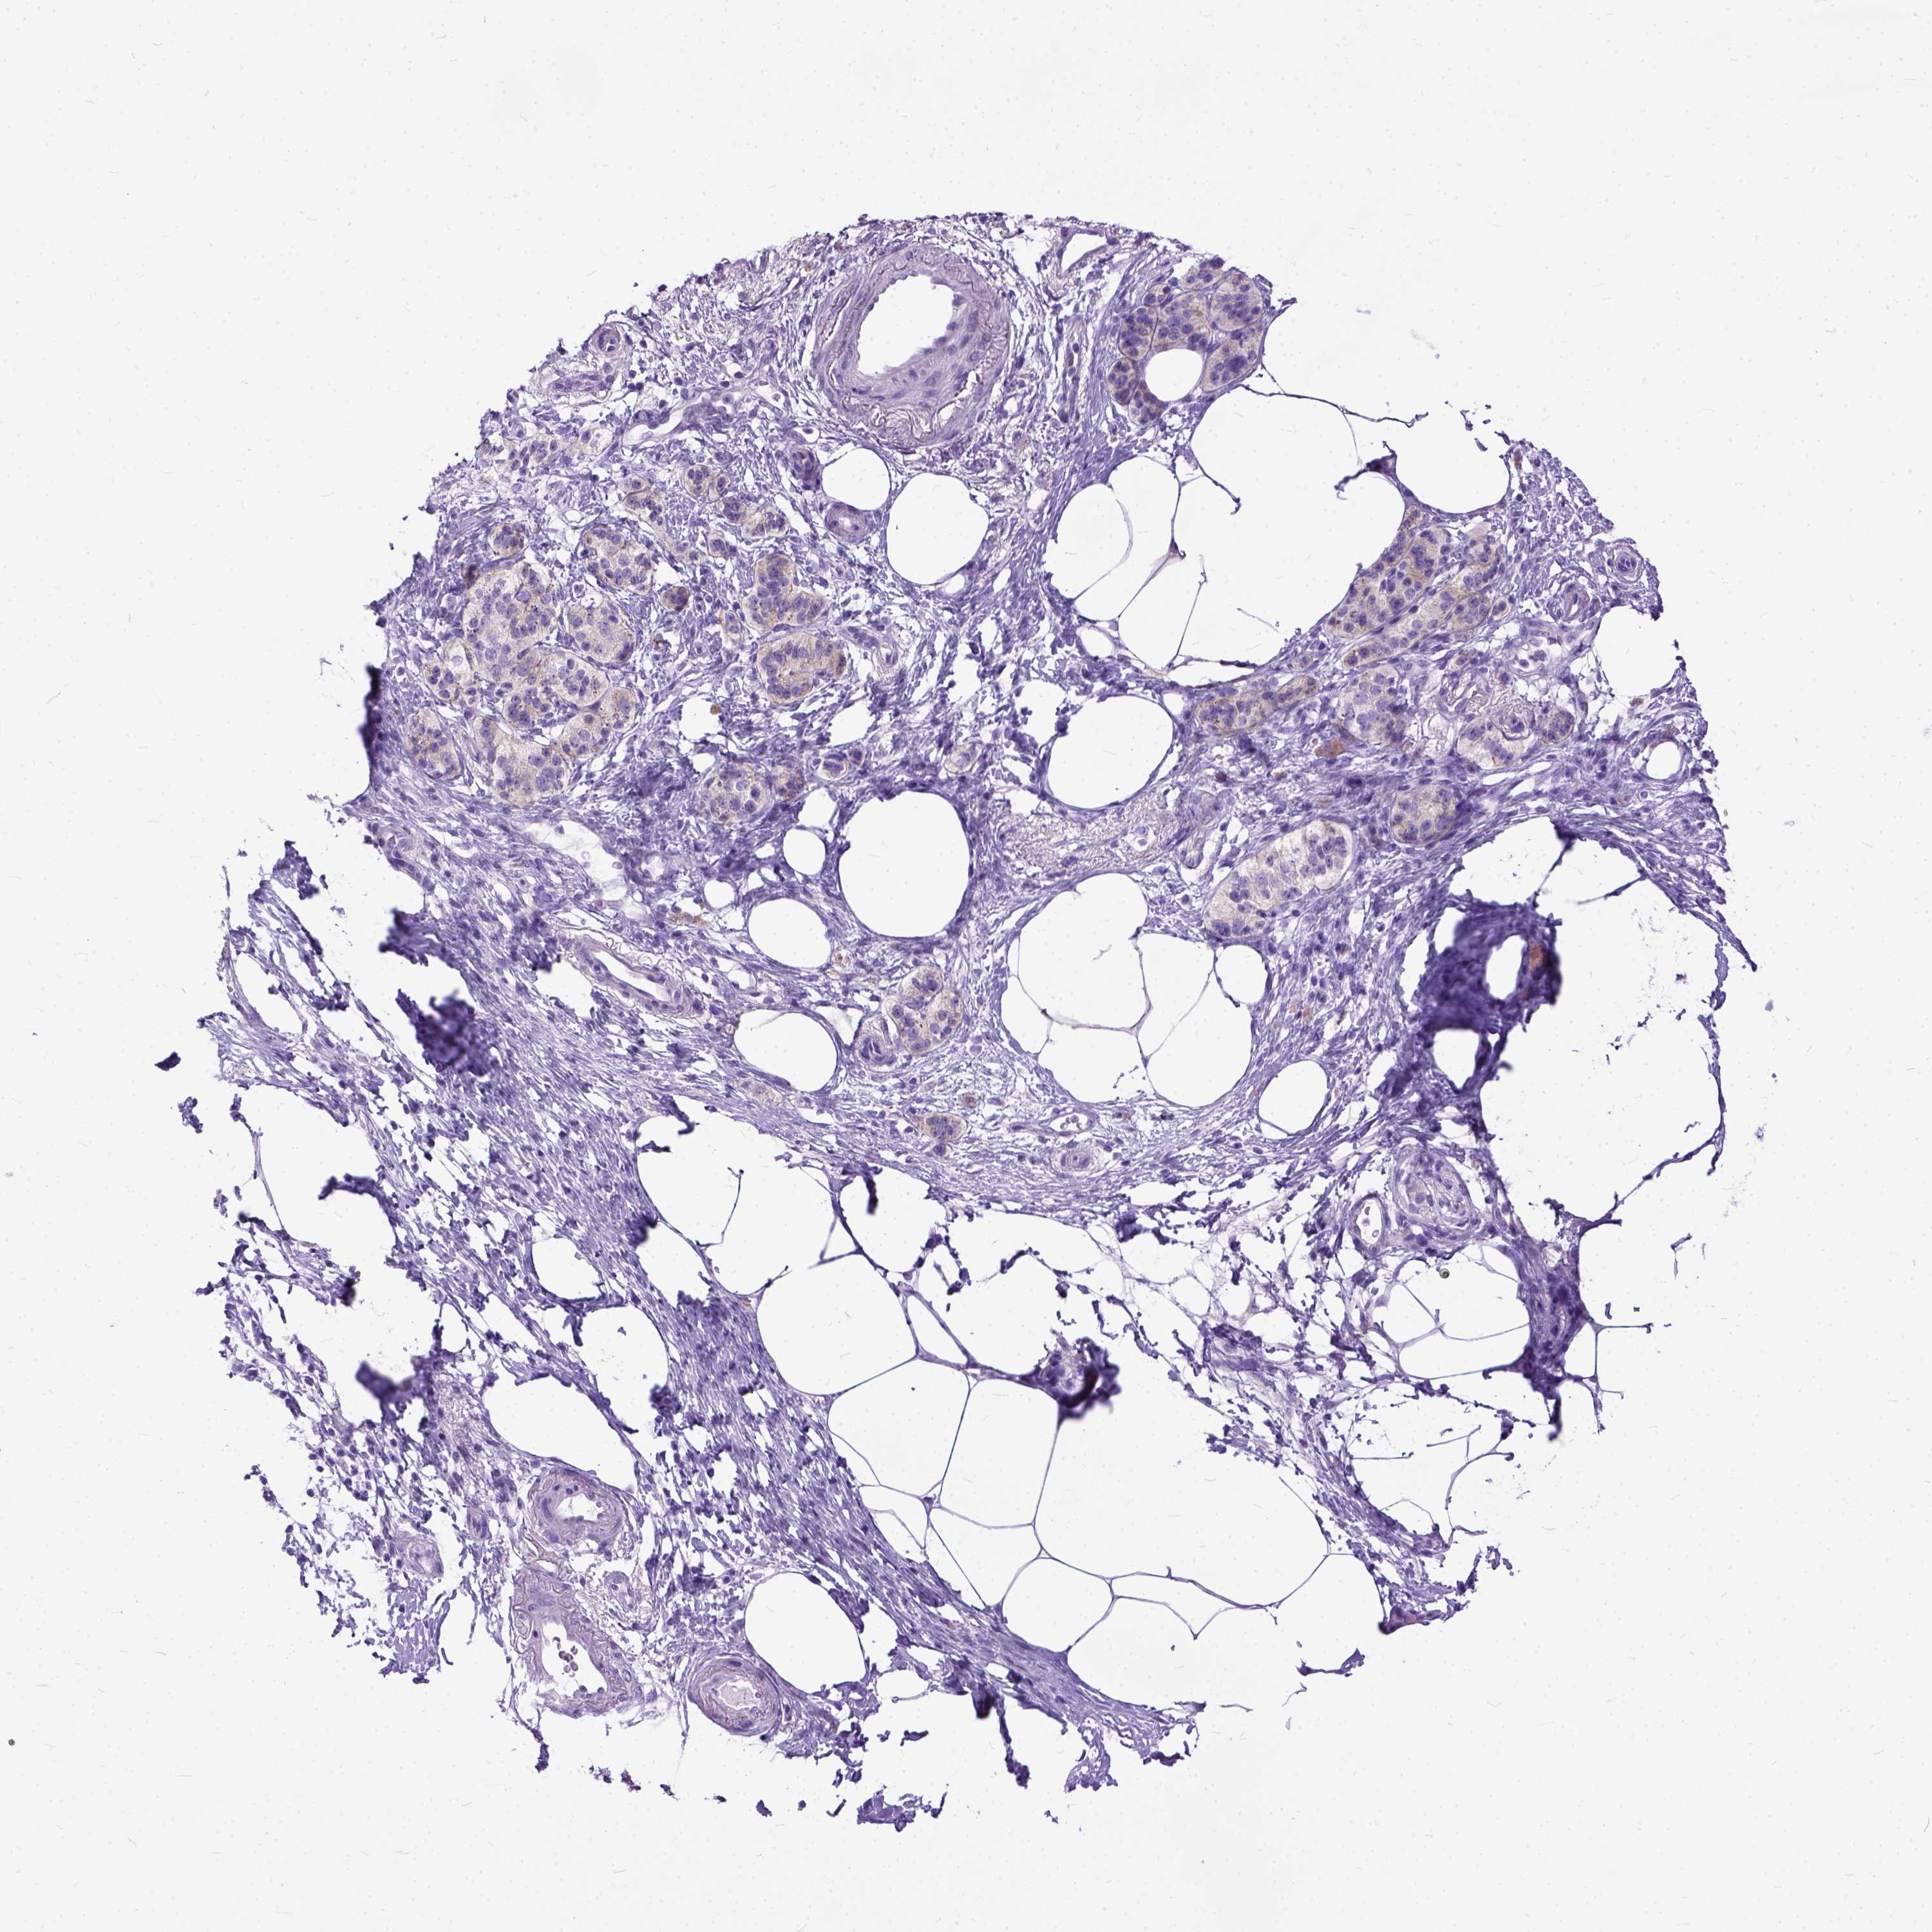

PANCREATIC CANCER - Protein expressioni

A mouse-over function shows sample information and annotation data. Click on an image to view it in a full screen mode. Samples can be filtered based on level of antibody staining by selecting one or several of the following categories: high, medium, low and not detected. The assay and annotation is described here.

Note that samples used for immunohistochemistry by the Human Protein Atlas do not correspond to samples in the TCGA dataset.

Antibody stainingi

Antibody staining in the annotated cell types in the current human tissue is reported as not detected, low, medium, or high, based on conventional immunohistochemistry profiling in selected tissues. This score is based on the combination of the staining intensity and fraction of stained cells.

Each image is clickable and will lead to virtual microscopy that enables deeper exploration of all samples and also displays staining intensity scores, fraction scores and subcellular localization as well as patient and tissue information for each sample.

Antibody HPA042550

Antibody HPA059859

Staining

High

Medium

Low

Not detected

Intensity

Strong

Moderate

Weak

Negative

Quantity

>75%

75%-25%

<25%

None

Location

Nuclear

Cytoplasmic/membranous

Cytoplasmic/membranous,nuclear

Adenocarcinoma, NOS